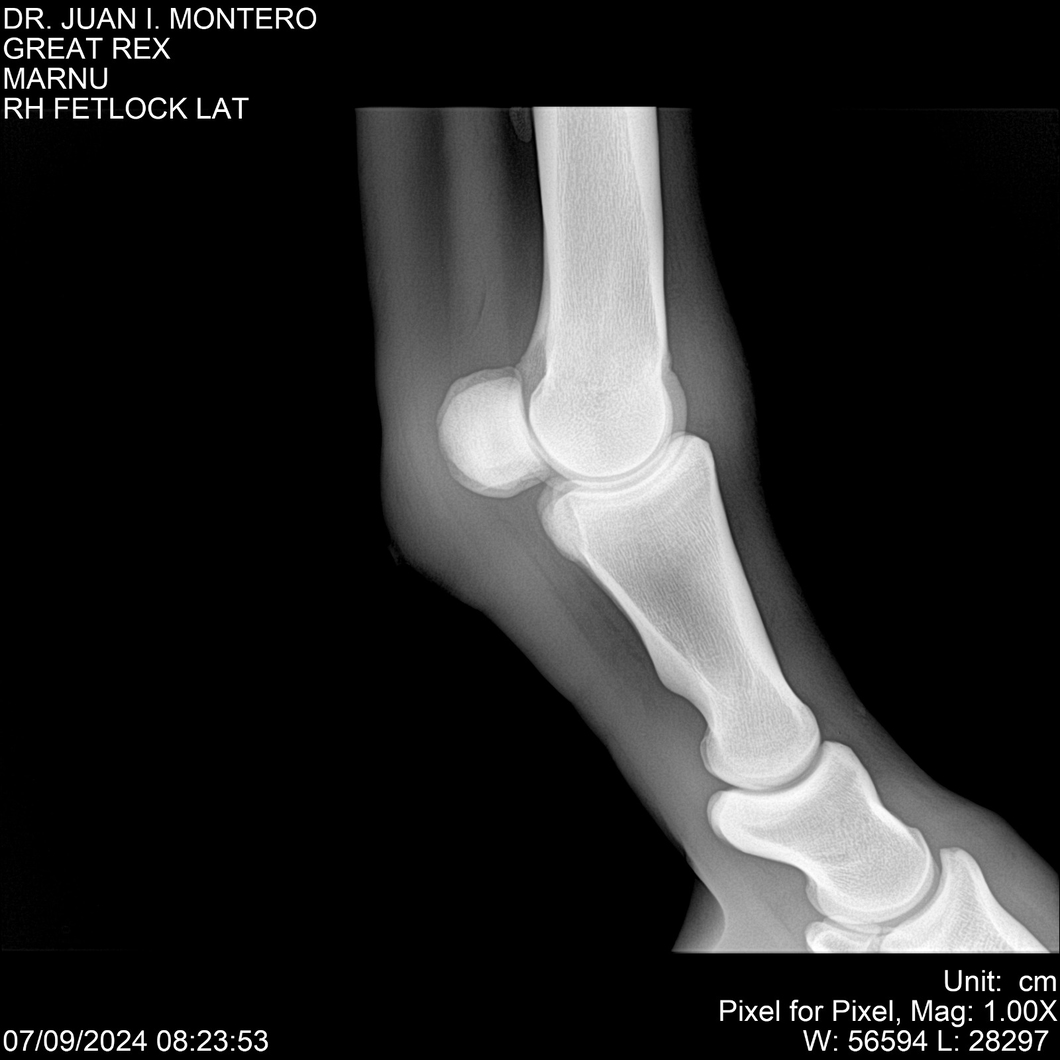

LOTE 4, GREAT REX Lote Anterior Volver al remate Lote Siguiente Ficha Contacto Montevideo - Ficha del Lote Identificador: #282518 Categoría: Yeguarizos Montevideo - 66 Visualizaciones ClicData Contacto Empresa: Abelenda N. R., Walter Hugo Nombre*: Teléfono* : E-mail* : Mensaje Enviar Registrese gratis Este contenido Exclusivo está disponible sólo para usuarios registrados Ingresar